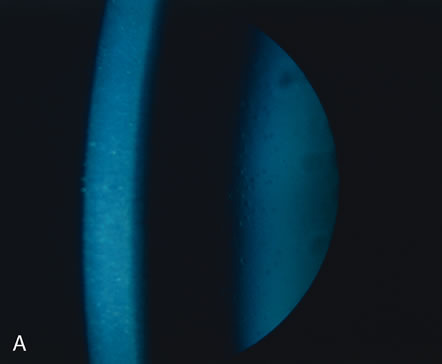

Fig. 25. Meesmann's corneal dystrophy. The characteristic slit lamp appearance is best demonstrated either by retroillumination (A) or through a red reflex (B). The latter best shows the increased distribution of tiny droplet-like lesions in the central cornea.

Histopathologically, numerous tiny intraepithelial cysts are seen, which result from the dissolution of the normal tonofibrillar skeleton of the epithelial cells.126,127 The full thickness of the epithelium is affected, with even the basal cells showing diffuse abnormalities. The matrix of the tonofibrils is composed of an abnormal complex containing a glycoprotein acid mucopolysaccharide compound that contains glycogen. Meesmann's corneal dystrophy is caused by mutations in the genes for cornea-specific cytokeratins K3 or K12.128,129